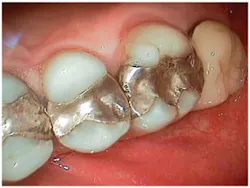

For instance, many patients, when given the option, may prefer to combine both immediate-need treatment with future-need treatment. Advantages of this approach include decreased chair time and fewer visits, impressions, and injections (Fig 4). From a restorative standpoint, we can often better manage the occlusion and blending of restorative materials for an optimal result when the dentistry is approached in a more integrated way.